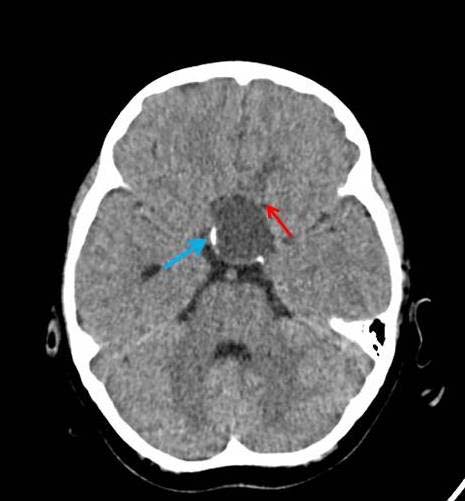

A 12-year-old girl presented with complaints of severe headache associated with vomiting for four days. She also gave a history of reduction in vision (Left>Right) and occasional mild headache of six months’ duration. She had no meningeal signs, fever nor neurological deficit. On examination, she was of short stature and Tanner Stage II [1]. Her ophthalmologic examination revealed a vision of 6/36 in the left eye and 6/6 in the right. Her lateral skull radiograph showed an enlarged sella turcica. Non-contrast enhanced CT showed a cystic lesion measuring 35 x 26 x 22 mm in supra-sellar region with presence of peripheral curvilinear calcification and oedema in left basifrontal region adjacent to cyst [Table/Fig-1]. Contrast enhanced CT revealed a larger peripherally enhancing cystic component in supra-sellar region with mild enhancement of intra-sellar solid component. T1 weighted MR imaging showed hyperintense cyst in supra-sellar location with isointense solid component in sellar location. There was also a hyperintense signal in the brain parenchyma antero-superior to cyst (left basifrontal region) [Table/Fig-2]. T2 weighted MR imaging revealed a well-defined cystic lesion in sellar-suprasellar location with oedema of left basifrontal lobe and adjacent discontinuity in cyst wall due to intra-parenchymal focal rupture of cyst [Table/Fig-3]. Compression and splaying of optic chiasma and optic tracts were also noted. The history, X-Ray, CT and MR imaging findings were suggestive of sellar-suprasellar craniopharyngioma with focal intra-parenchymal rupture of the cyst antero-superiorly into left basifrontal lobe. This rupture of the craniopharyngioma cyst intra-parenchymally causing excruciating headache is the unique presenting feature of this case.

Axial NECT showing cystic lesion measuring 3.5 x 2.6 x 2.2 cm in suprasellar region with presence of curvilinear calcification (blue arrow) with mild oedema of left basifrontal lobe (red arrow).